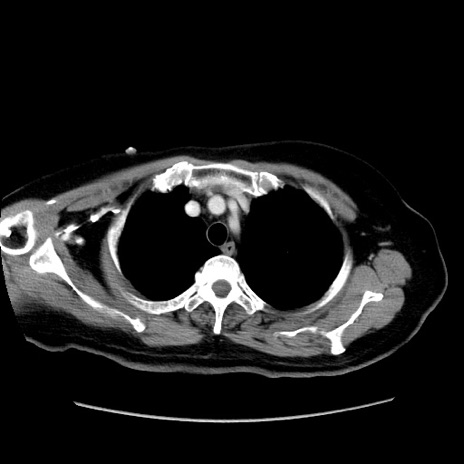

症例19(横断像)

【症例】80歳代女性

【主訴】下腹部痛

【現病歴】約8時間前より下腹部痛の出現あり、救急外来受診。

【既往歴】両側付属器切除

【身体所見】意識清明、下腹部正中に手術痕あり、その部位に一致して圧痛と反跳痛あり。腸蠕動音は亢進。

【データ】WBC 9300、CRP 0.15